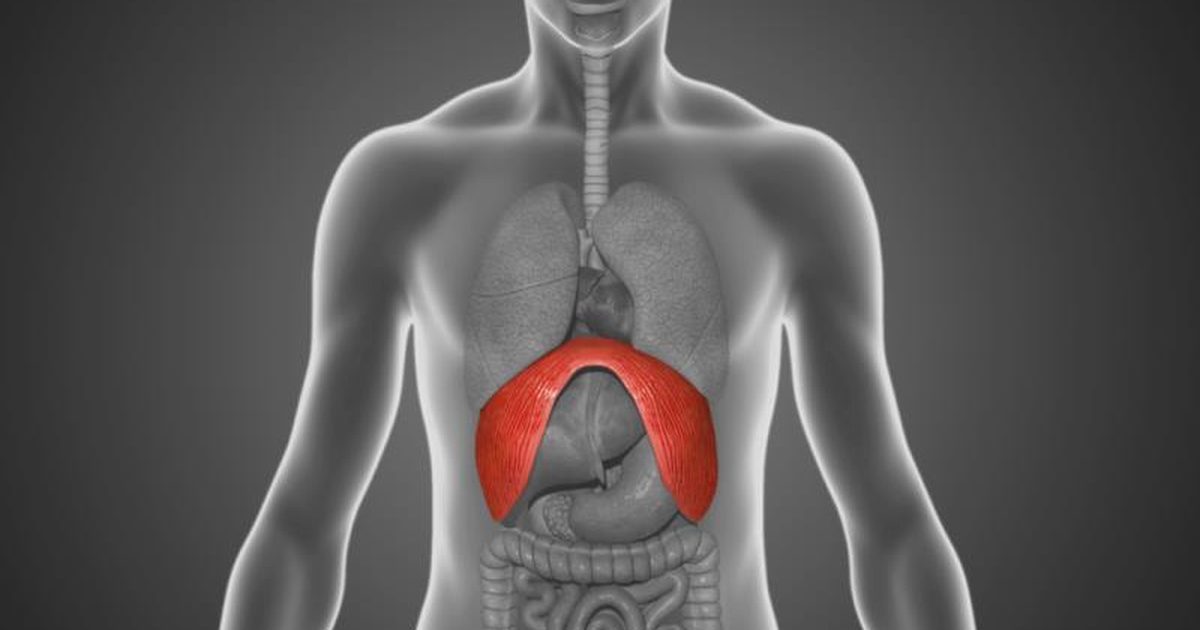

Анатомия диафрагмы и треугольника Бохдалека

Раздел: Визуальный дайджест